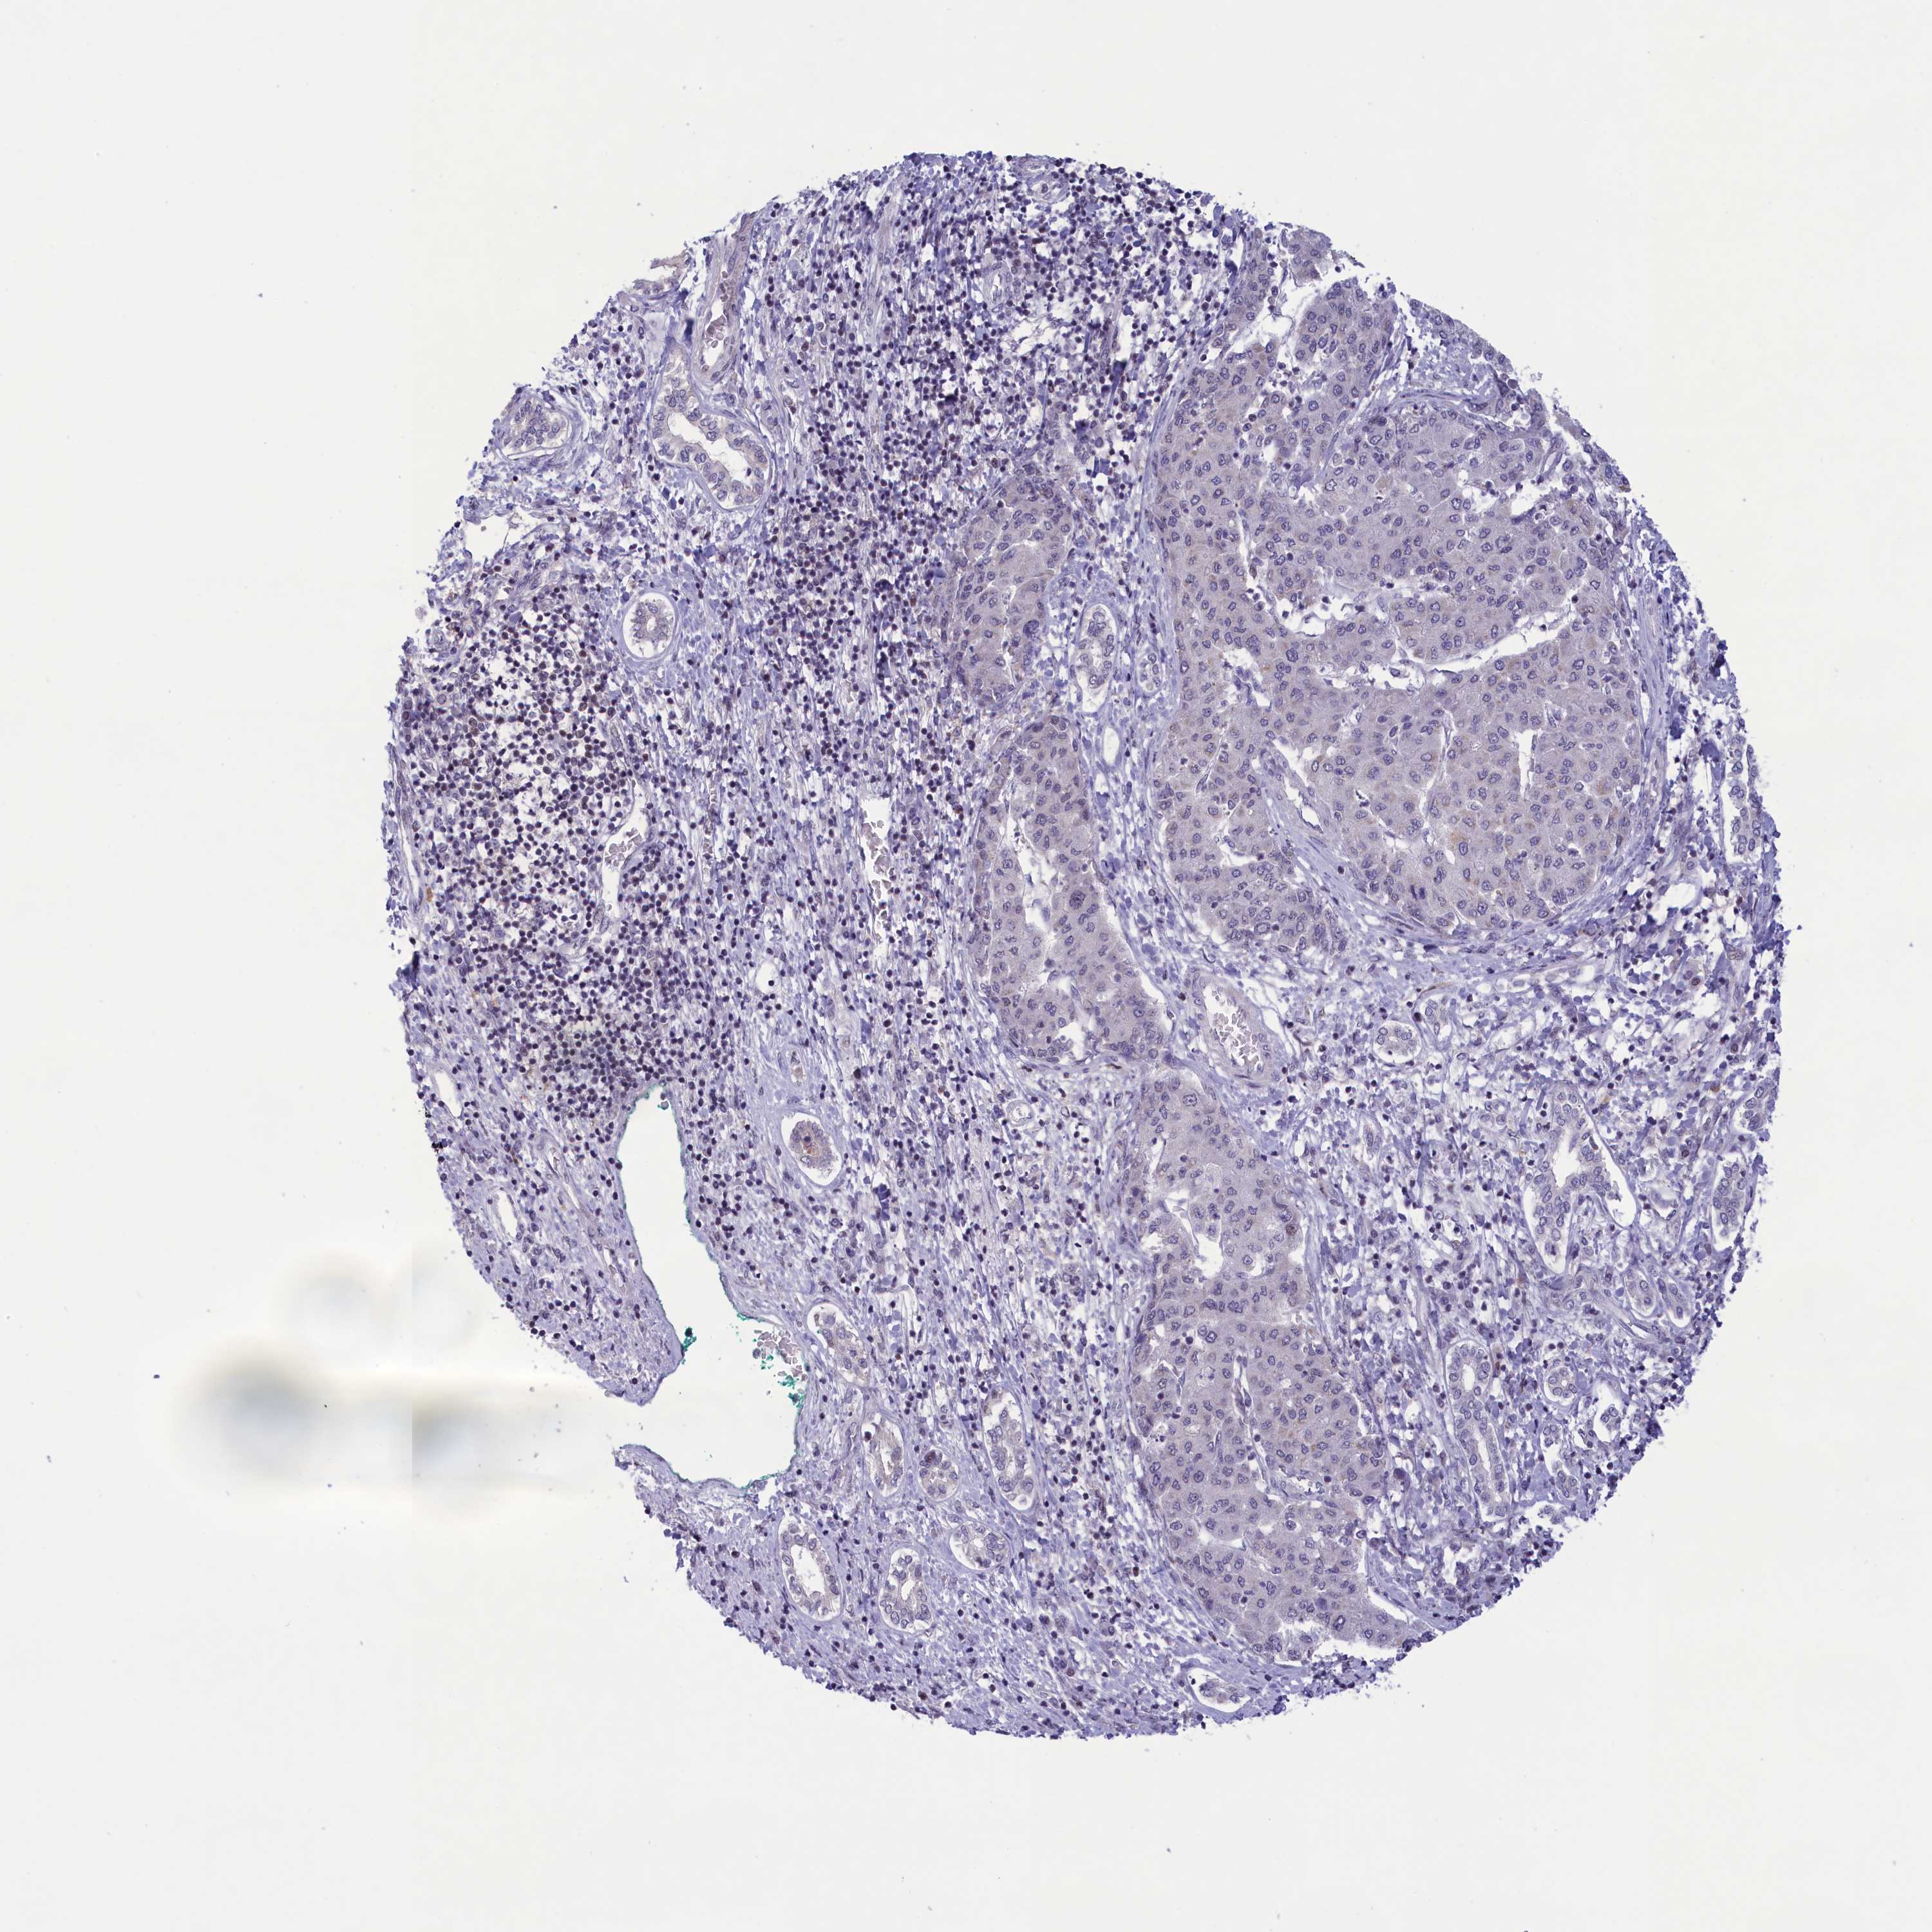

LIVER CANCER - Protein expressioni

A mouse-over function shows sample information and annotation data. Click on an image to view it in a full screen mode. Samples can be filtered based on level of antibody staining by selecting one or several of the following categories: high, medium, low and not detected. The assay and annotation is described here.

Note that samples used for immunohistochemistry by the Human Protein Atlas do not correspond to samples in the TCGA dataset.

Antibody stainingi

Antibody staining in the annotated cell types in the current human tissue is reported as not detected, low, medium, or high, based on conventional immunohistochemistry profiling in selected tissues. This score is based on the combination of the staining intensity and fraction of stained cells.

Each image is clickable and will lead to virtual microscopy that enables deeper exploration of all samples and also displays staining intensity scores, fraction scores and subcellular localization as well as patient and tissue information for each sample.

Antibody HPA041161

Antibody HPA041302

Staining

High

Medium

Low

Not detected

Intensity

Strong

Moderate

Weak

Negative

Quantity

>75%

75%-25%

<25%

None

Location

Nuclear

Cytoplasmic/membranous

Cytoplasmic/membranous,nuclear

Cholangiocarcinoma

Carcinoma, Hepatocellular, NOS